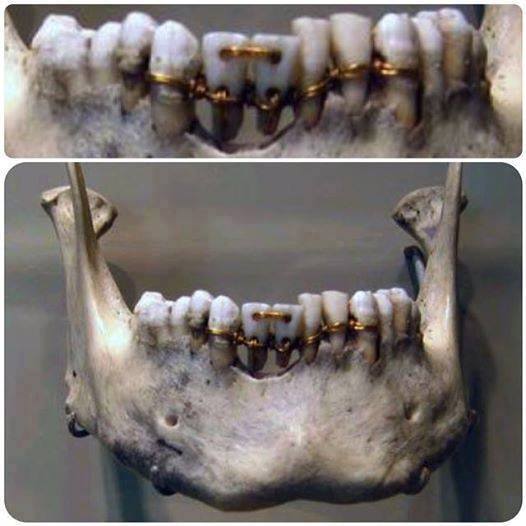

روزی ک فکرکردی یک چیزی رواز ته دل دوست داری هیچوقت ولش نکن ممکنه دوباره تکرار نشه یک پژوهشگر رشته ریاضی از کشور هلند موفق به شناسایی یک شاهکار مهندسی در طراحی و ساخت گنبد آرامگاه«شاه نعمت الله ولی» (واقع در ماهان کرمان) شد که اکنون معمای عدد 11 را در مقابل استادان معماری قرار می دهد. «وینسنت کارلز»(Vincent Karels) افزود: بر اساس مطالعاتی که بر روی طرح گنبد فیروزه ای این آرامگاه انجام دادم، پی بردم که این گنبد به 11 قسمت مساوی تقسیم شده است. این دندانها متعلق به یک مومیایی است که دندانهایش را با طلا ترمیم کرده و مومیایی او در مصر کشف شده است. گفتارنیوز:در گذشته برای ترمیم دندانها از طلا استفاده میکردند و با سوراخ کردن دندانها سیمهایی از جنس طلا را در بین دندانها جای می دادند.

پژوهشها نشان میدهد این روش درمانی اگرچه برای مدت زمان کوتاهی باعث بهبودی دندان ها و مشکلات دهان میشد اما پس از مدتی بر اثر عفونت فرد جان خود را از دست میداد.

این روش درمانی اکنون نیز در سرزمین هایی دور افتاده که امکانات و تجهیزات درمانی بسیار کم است.